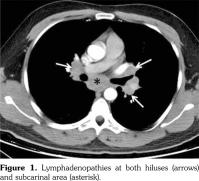

A 29-year-old male patient who had AS for 13 years applied to our rheumatology outpatient clinic for routine yearly control. His AS had been under control with etanercept for 43 months. After the routine follow-up evaluation, a thorax computed tomography scan was performed because of hilar enlargement in the chest X-ray. Multiple lymphadenopathies, the largest one with 2 cm in diameter, were detected in computed tomography scan (Figure 1).